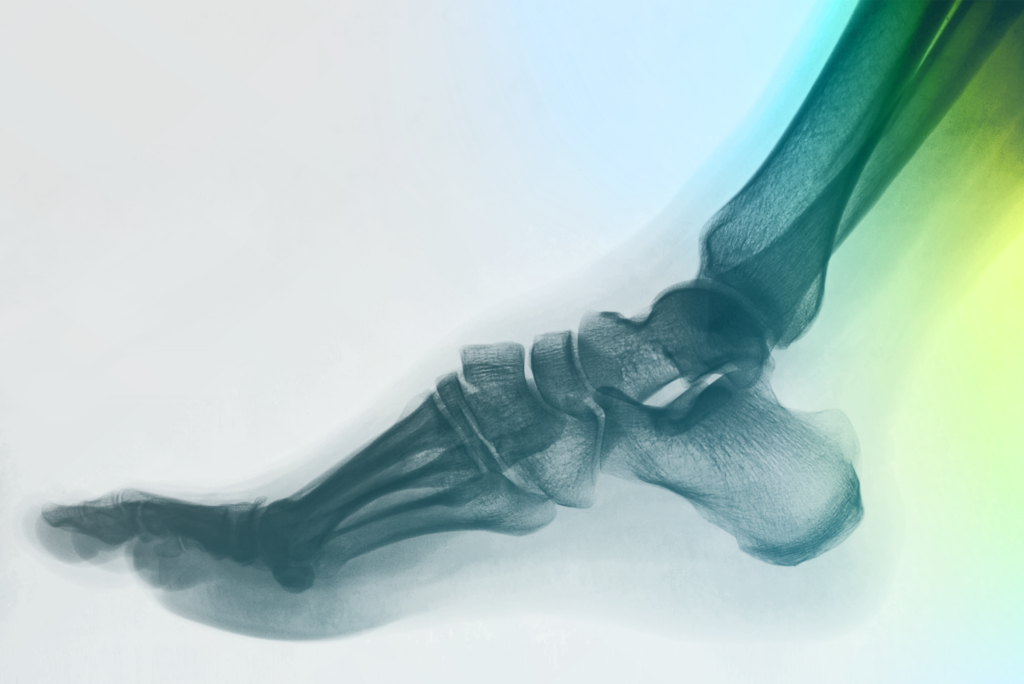

Ankle Surgery

Medical procedure addressing various ankle joint issues. Includes thorough assessment followed by personalized treatment selection considering patient-specific needs for stability and proper function.

Foot Surgery

Addresses complex foot structure issues (26 bones, 33 joints). Treats deformities affecting feet and toes to maintain stability and movement for daily activities.